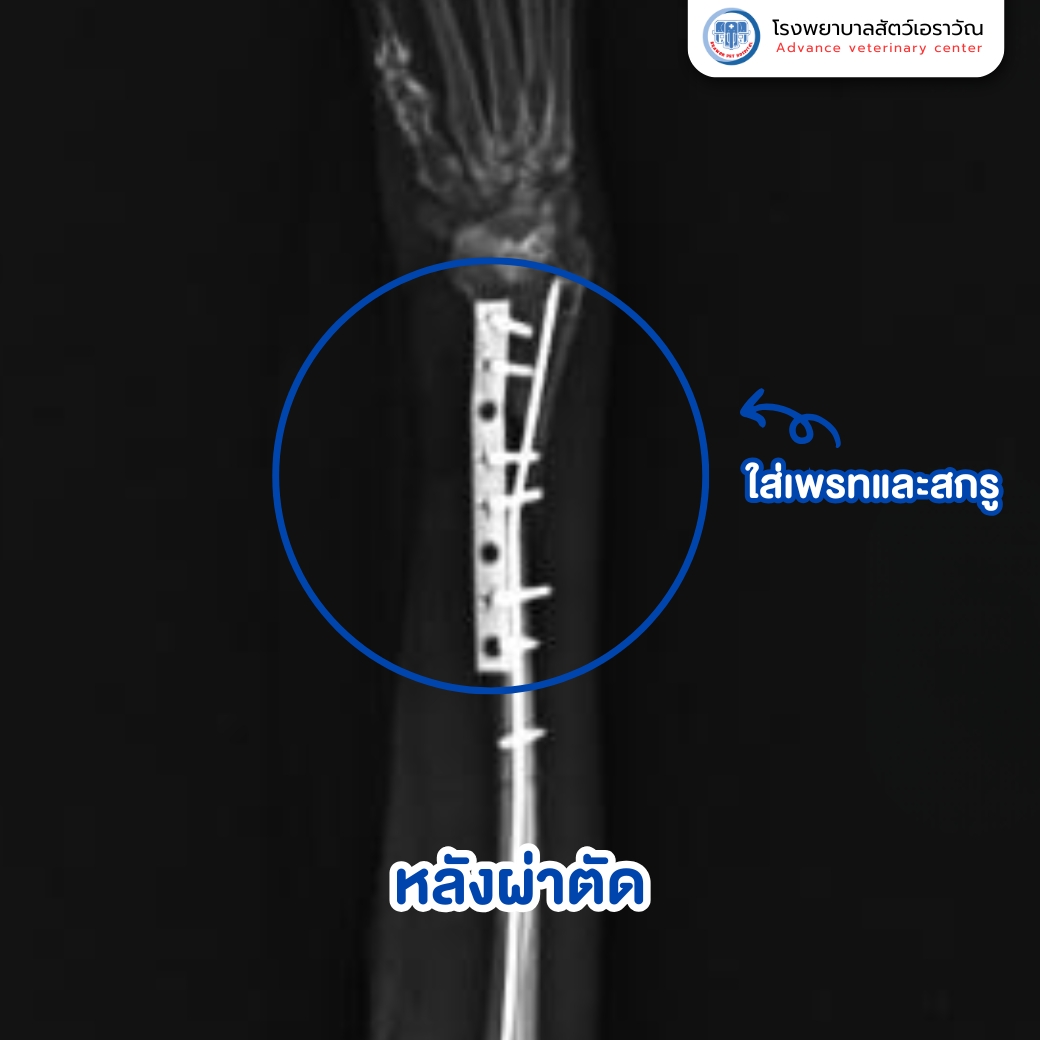

การผ่าตัดดำเนินไปอย่างราบรื่น ใช้เทคนิคการยึดกระดูกแบบ internal fixation ด้วยแผ่นเพลทและสกรูขนาดเล็กพิเศษ สำหรับสัตว์เล็กโดยเฉพาะ หลังผ่าตัด น้องแมวได้รับการดูแลอย่างใกล้ชิดใน ห้อง CCU (Critical Care Unit) ที่มีทีมสัตวแพทย์และพยาบาลประจำตลอด 24 ชั่วโมง คอยสังเกตอาการและดูแลเรื่องยา ป้อนอาหาร รวมถึงลดความเครียดหลังผ่าตัด

ในระยะเวลาไม่กี่วัน น้องแมวเริ่มยืนและเดินได้ดีขึ้น และสามารถกลับบ้านได้อย่างปลอดภัย โดยมีการนัดตรวจติดตามอาการต่อเนื่อง